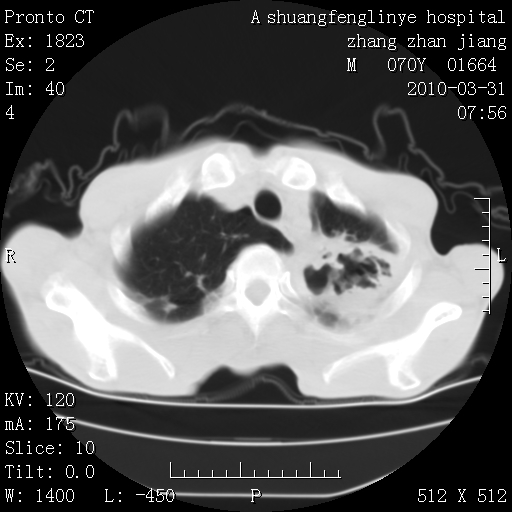

双上肺继发型tb并左上空洞形成,主动脉冠脉钙化。

支持:继发性肺结核伴空洞形成!建议纤支镜检查待出外周围型肺癌可能!

1)两肺上叶继发性肺结核并左肺上叶空洞形成。2)冠状动脉及主动脉钙化。